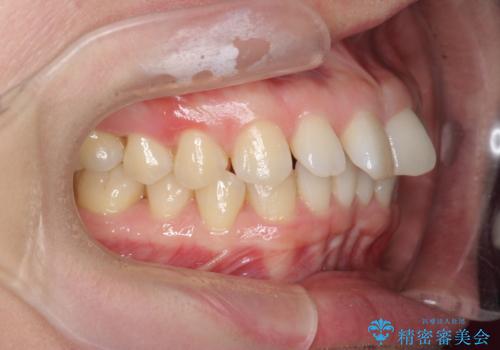

インビザライン で治す 出っ歯の治療

- 前歯の突出感、出っ歯の治療を希望され来院されました。

インビザラインを用いた治療計画を立て、しっかりと出っ歯を治すためにマイクロインプラントを併用します。

マイクロインプラントを併用することでしっかりとマウスピース全体を後方へ引き、前歯の突出感を改善することができました。